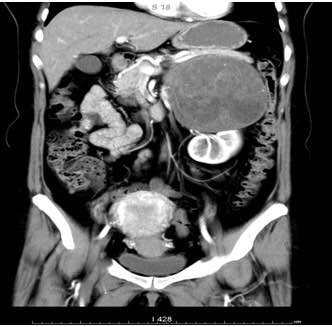

这个肿瘤直径21厘米,长在左侧肾脏上方的位置,周围血管丰富,与下腔静脉、肠系膜上、下静脉、脾动静脉、左肾动静脉关系密切,手术难度极高,术中稍有不慎便会危及生命。

2018年4月23日,王强主任麻醉,徐青主任主刀,第一助手刘文国副主任医师,第二助手石青青医师,第三助手范荣富医师,成功开腹后一个庞然大物出现在医生们的眼前,肿瘤与下腔静脉、肠系膜上、下静脉、脾动静脉、左肾动静脉粘连较重,这些血管像八爪章鱼一样将肿瘤紧密缠绕在中间,肿物内有血肿和血块形成,术中测量肿瘤最大直径达21厘米。徐青主任带领团队成员密切配合,耐心细致的将下腔静脉、肠系膜上、下静脉、脾动静脉、左肾动静脉与肿瘤剥离开来。